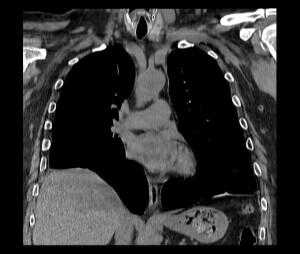

Через 3 сут после травмы после стабилизации состояния и контрольной рентгенографии груди (рис. 1) пострадавший переведен на спонтанное дыхание и экстубирован, дренаж из правой плевральной полости удален. Рисунок 1. Рентгенограммы груди. а - 2-е сутки после травмы; б - 6-е сутки после травмы. Тяжесть состояния в этот момент определялась черепно-мозговой травмой и дыхательной недостаточностью I степени. При аускультации дыхание было ослаблено справа в базальном отделе. При рентгенографии на 6-е сутки после операции отмечены нечеткость контура и высокое расположение правой половины диафрагмы - на уровне переднего отрезка III ребра. При УЗИ подтверждено высокое расположение правой половины диафрагмы и обнаружен ее дефект с перемещением части печени в правую плевральную полость (рис. 2). Рисунок 2. Эхограмма правой плевральной полости на 6-е сутки после травмы. 1 - неповрежденный участок диафрагмы; 2 - печень, переместившаяся в правую плевральную полость через разрыв диафрагмы; 3 - жидкость в правой плевральной полости.

Пострадавший экстренно оперирован под эндотрахеальным наркозом с раздельной вентиляцией легких. В положении на левом боку с учетом высокого расположения правой половины диафрагмы выполнен разрез кожи в четвертом межреберье по правой переднеподмышечной линии длиной 1,5 см. Разведены мышцы, в плевральную полость введен торакопорт 10,5 мм, камера 30°. В плевральной полости 300 мл геморрагической жидкости. Правая половина диафрагмы расположена на уровне пятого межреберья, визуализирован ее разрыв, идущий справа налево, спереди назад от границы мышечной части и сухожильного центра к перикарду. Размеры разрыва 6×8 см, через него в плевральную полость частично пролабирует правая доля печени, на которой имеется несколько некровоточащих разрывов капсулы (рис. 3). Рисунок 3. Операционные фотографии. а - разрыв диафрагмы с дислокацией печени в правую плевральную полость; б - ушитый разрыв диафрагмы. Дополнительные торакопорты 10,5 мм установлены в пятом межреберье по среднеключичной и шестом межреберье по заднеподмышечной линии. Печень низведена в брюшную полость с помощью эндоскопического ретрактора. Произведено ушивание разрыва диафрагмы отдельными узловыми швами инструментом Endo Stitch нитью Surgidac USP 0 с экстракорпоральной вязкой узлов. Дренажи диаметром 8 мм в задний костодиафрагмальный синус и к верхушке гемиторакса выведены через проколы для торакопортов в шестом и четвертом межреберьях соответственно. Легкое расправлено под визуальным контролем. Пострадавший экстубирован по окончании операции.

На рентгенограмме после операции правая половина диафрагмы четкая, на уровне переднего конца V ребра (рис. 4), при УЗИ свободной жидкости в плевральной полости нет, диафрагма четкая, печень расположена в брюшной полости (рис. 5). Рисунок 4. Рентгенограмма груди после операции. Рисунок 5. Эхограмма правой плевральной полости после операции. 1 - правая половина диафрагмы; 2 - печень. Послеоперационный период протекал без осложнений. Дренажи удалены на 3-и сутки после операции, раны зажили первичным натяжением.